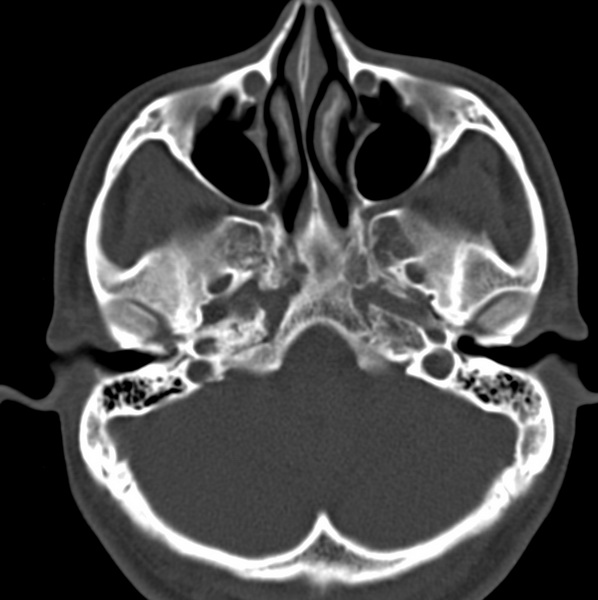

男、31、鼻咽部肿瘤放疗后请帮忙看看。

效果好,右侧破裂孔扩大,局部骨质缺损,为颅底骨质破坏。

1)鼻咽部肿瘤侵犯颅底放疗术后改变。2)左侧蝶窦炎。

咽后壁增厚,左侧咽鼓管隆突增大、咽鼓管咽口变浅,同侧咽旁间隙较窄。右侧颅底骨质破坏?为什么不在同一侧?

鼻咽部肿瘤侵犯颅底放疗术后改变.